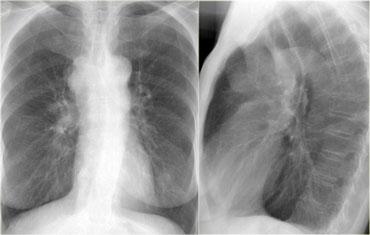

Mất khoang sáng sau xương ức

Hãy mô tả các hình ảnh bên trái.

Sau đó tiếp tục.

Trên phim thẳng (PA), có hình ảnh giãn rộng dạng múi của trung thất trên.

Trên phim nghiêng ngực, khoang sáng sau xương ức bị xóa mờ.

Đây là trường hợp bệnh nhân mắc u lympho.

Bên trái là hình ảnh FDG-PET của cùng bệnh nhân.

Có nhiều khối hạch bạch huyết ở trung thất trước, trung thất giữa và thậm chí trung thất sau, lan lên vùng cổ.